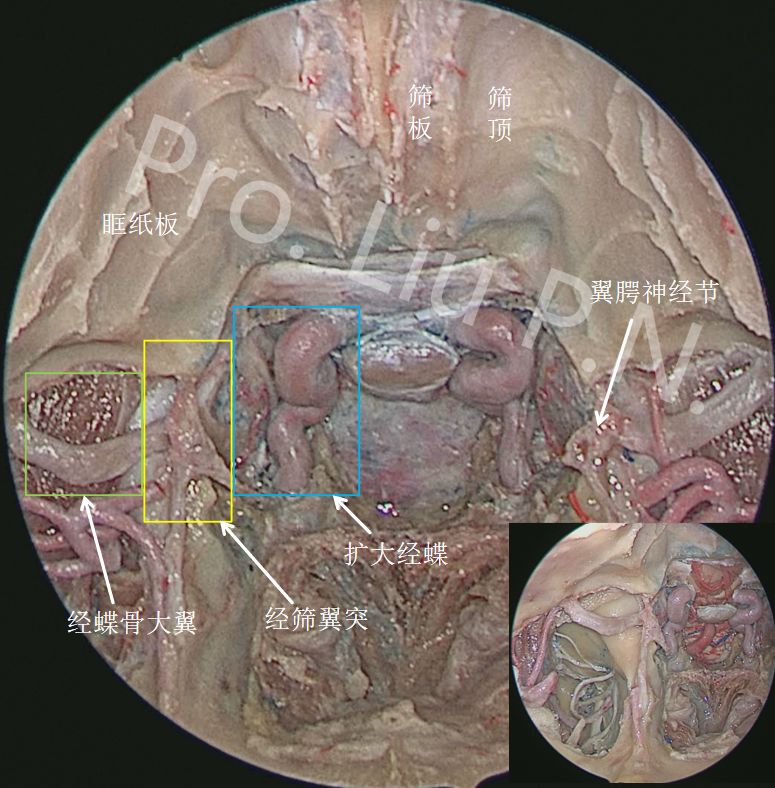

十一、经上颌窦-蝶骨大翼-海绵窦

入路内镜解剖

![]()

切断翼外肌上、下头在翼突外侧板的附着点,外翻翼外肌上、下头,清理肌间隙内静脉丛及骨膜,显露蝶骨大翼腹侧面

去除左侧翼突及蝶骨大翼骨质,显左侧露海绵窦外侧壁、前壁、卵圆孔、颞极、咽鼓管及咽旁间隙